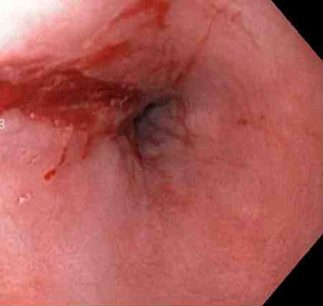

[Figure caption and citation for the preceding image starts]: Actively bleeding tear appears as a red longitudinal defect with normal surrounding mucosaFrom the collection of Juan Carlos Munoz, MD, University of Florida [Citation ends].

Actively bleeding lesions. [Figure caption and citation for the preceding image starts]: Bleeding Mallory Weiss Tear viewed on retroflexionFrom the personal collection of Douglas Adler; used with permission [Citation ends].